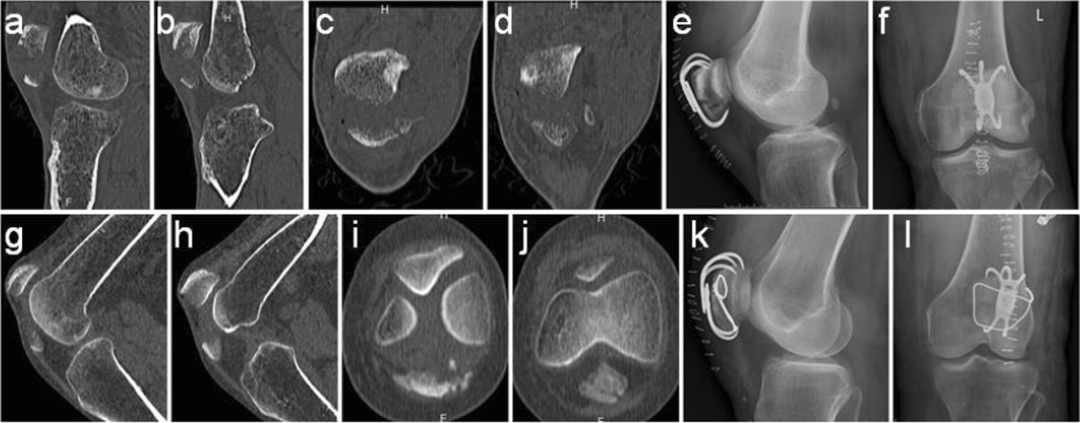

图3. 对照组和实验组患者复位前后的比较。

a - f : 38岁,男性,入院前3小时因摔伤导致骨折入院。a-b术前CT检查矢状面。c-d术前冠状面CT检查。e-f术后x线片。

g-l:一名65岁女性,入院前5小时因跌倒导致骨折。g-h术前矢状面CT检查。i-j术前冠状面CT检查。k-l术后x线片。